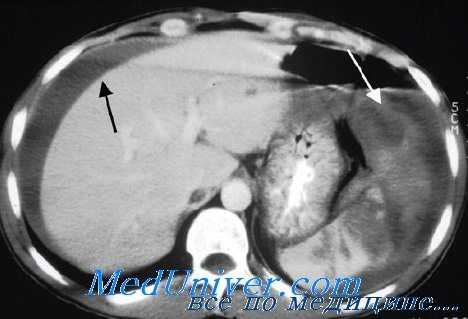

КТ – диагностика повреждений паренхиматозных органов, аорты, очагов кровоизлияний в брюшной полости и забрюшинном пространстве. Использование рентгеноконтрастных веществ (в/в или внутрь) расширяет возможности КТ и позволяет одновременно визуализировать паренхиматозные и полые органы брюшной полости. Повреждения почек и забрюшинные гематомы выявляют с помощью КТ живота, которую нужно провести каждому больному с гематурией и стабильной гемодинамикой (Уровень рекомендации - C)[3]. Необходимость проведения ИВЛ пациенту не является противопоказанием к КТ. Противопоказание - нестабильная гемодинамика пациента. Когда имеется подозрение на повреждение печени/селезенки КТ позволяет исключить повреждения требующие экстренного оперативного вмешательства (Уровень рекомендации - В) [3]. КТ рекомендуется у гемодинамически стабильных пациентов с неоднозначными данными физикального осмотра, сочетанной неврологической травме или множественной экстраабдоминальной травме. При негативном результате КТ пациент госпитализируется для динамического наблюдения (уровень доказательства – I) [5]. КТ позволяет выбрать консервативную тактику ведения у пациентов с солидным характером повреждения внутренних органов (уровень доказательства – I) [5]. У гемодинамически стабильных пациентов ДПЛ и КТ являются дополняющими друг друга методами диагностики (уровень доказательства – I) [5]. КТ не может использоваться как единственный метод диагностики для исключения повреждений кишки, диафрагмы, поджелудочной железы (Уровень рекомендации - В) [3]. КТ БП достоверно идентифицирует гемоперитонеум у пациентов с ТТЖ (Уровень рекомендации - В)[3]. Пероральное введение контраста при КТне является обязательным при диагностике ТТЖ (Уровень рекомендации - В) [3].

Объективным результатом КТ, перспективным в качестве прогностического фактора неоперативного лечения является затемнение в поврежденной паренхиме селезенки. Считается, что такое затемнение означает продолжающееся кровотечение, когда наблюдается вскоре после травмы, и псевдоаневризму, когда наблюдается на поздних снимках. Имеются доказательства, что при наличии этого признака шансы на последующее успешное неоперативное лечение существенно уменьшаются.

Контрастную «кляксу» при первичной КТ нужно оценить с помощью ангиографии и, при продолжающемся кровотечении приенить эмболизацию, если имеется такая возможность. Контрастная «клякса» связана с более высокой потребностью в оперативном вмешательстве (67% против 6% у взрослых, 22% против 4% у детей). Этот подход представляется резонным, так как ангиография с эмболизацией сосудов селезенки увеличивает частоту успеха у пациентов, которых лечили консервативно. Наиболее заметное улучшение наблюдается у пациентов с повреждениями селезенки тяжелой степени. Доступные данные показывают увеличение успеха неоперативного лечения с 67% до 83% при повреждениях IV степени и с 25% до 83% при повреждениях V степени.